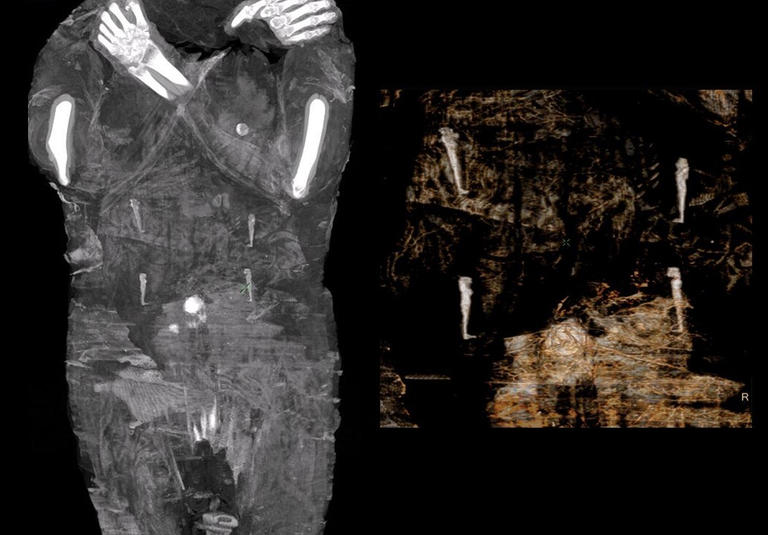

وأضافت: “تم إخضاع المومياء لعدة مجموعات من التصوير المقطعي والأشعة السينية وتصور ثلاثي الأبعاد مما سمح بفحص دقيق للجنين بأكمله والذي أثبت أن المرأة كانت في الأسبوع 26-28 من الحمل”.

وأوضح فريق البحث أن” اكتشاف المومياء الفرعونية، التي كان يُعتقد في البداية أنها جثة الكاهن حور جيهوتي، كانت أنثى في الواقع، وأظهر البحث أن المرأة في الضمادات، هي حامل”.

ولأسباب غير معروفة، لم يتم إخراج الجنين من بطن المتوفية أثناء التحنيط، ولهذا السبب تعتبر هذه المومياء مميزة حقا.. هذا يعني أن مومياءنا هي الوحيدة المعترف بها حتى الآن في العالم والتي يوجد بها جنين في الرحم”.

ويتراوح عمر المرأة بين 20 و30 عاماً، ووفقاً لتقديرات العلماء، وقالوا إن حجم جمجمة الطفل يشير إلى أنها كانت في الأسبوع 26 إلى 28 من الحمل.